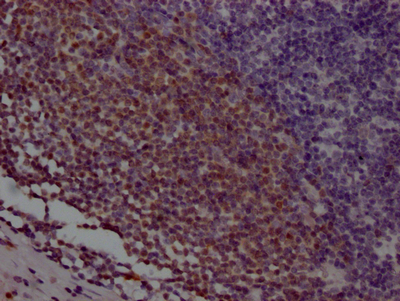

IHC image of CSB-RA280291A0HU diluted at 1:100 and staining in paraffin-embedded human tonsil tissue performed on a Leica BondTM system. After dewaxing and hydration, antigen retrieval was mediated by high pressure in a citrate buffer (pH 6.0). Section was blocked with 10% normal goat serum 30min at RT. Then primary antibody (1% BSA) was incubated at 4℃ overnight. The primary is detected by a Goat anti-rabbit IgG polymer labeled by HRP and visualized using 0.05% DAB.

IHC image of CSB-RA280291A0HU diluted at 1:100 and staining in paraffin-embedded human appendix tissue performed on a Leica BondTM system. After dewaxing and hydration, antigen retrieval was mediated by high pressure in a citrate buffer (pH 6.0). Section was blocked with 10% normal goat serum 30min at RT. Then primary antibody (1% BSA) was incubated at 4℃ overnight. The primary is detected by a Goat anti-rabbit IgG polymer labeled by HRP and visualized using 0.05% DAB.